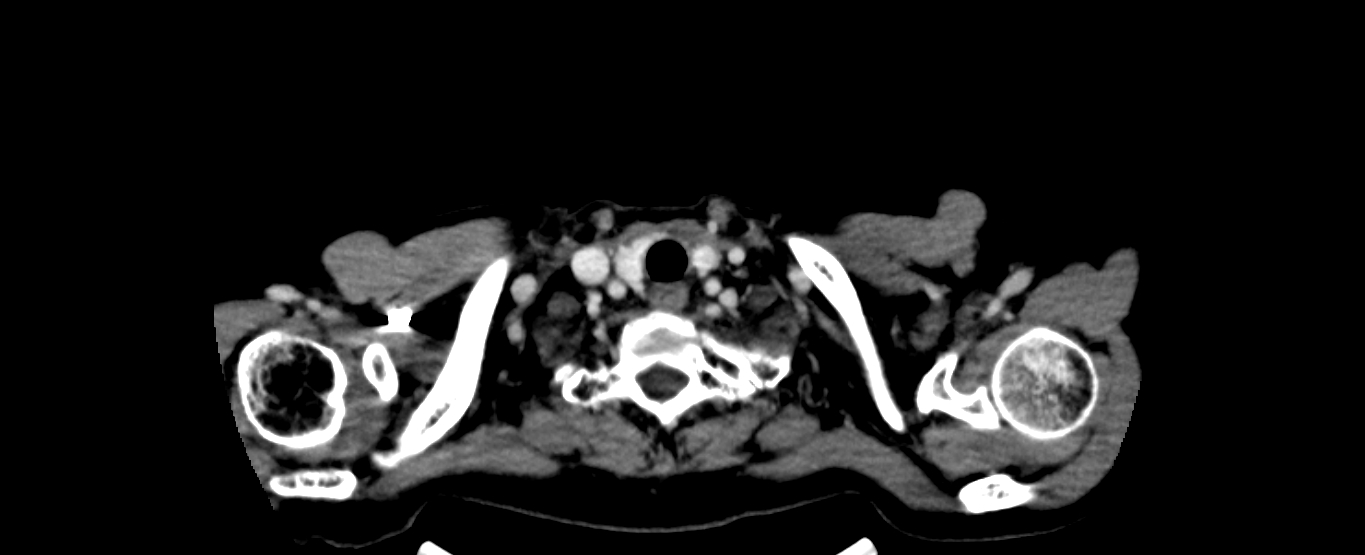

患者黄某某,女,56岁,食管中分化鳞癌患者,因吞咽困难检查发现食管癌,予以食管癌根治性调强放疗,巨大食管肿瘤消退明显,疗效良好,目前患者能够正常进食,体重逐渐恢复。

放疗后CT: